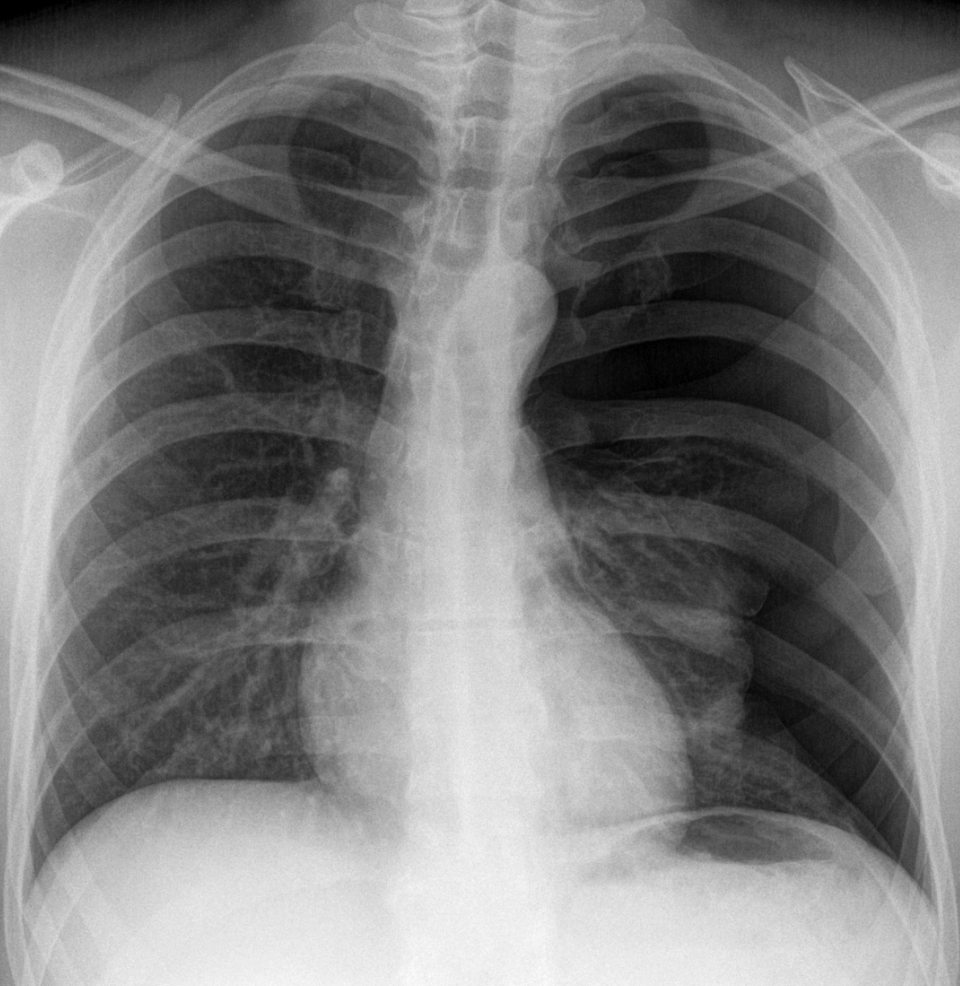

Wird beim Spontanpneumothorax eine Thoraxdrainage gelegt, kommt es in 20–35 % der Fälle zum Rezidiv. Wird beim Spontanpneumothorax eine Thoraxdrainage gelegt, kommt es in 20–35 % der Fälle zum Rezidiv. © wikimedia/Hellerhoff (CC BY-SA 3.0)